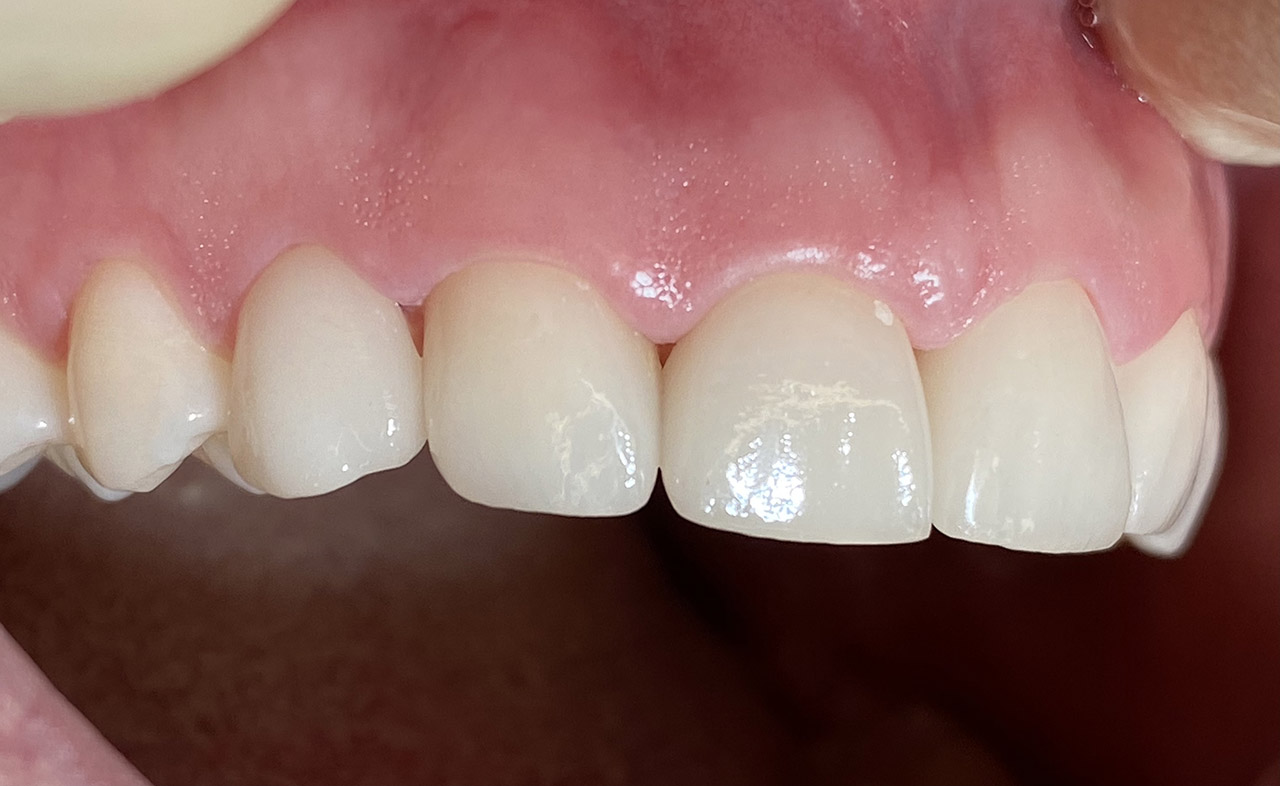

Internes und Externes Bleaching (Bleichen):

Nach Unfall mit E-Scooter unbefriedigendes Ergebnis der Erstversorgung (alio loco). Therapievorschlag: Stiftzähne?

Unsere minimalinvasive Therapie: Revision der Wurzelbehandlungen, danach internes und externes Bleaching, adhäsive Kunststoffüllungen in Schichttechnik. (Titel meiner Diplomarbeit 2003 “Die Vermeidung von Extraktion und Wurzelspitzenresektion durch zeitgemässe Endodontie in der Privatpraxis”)